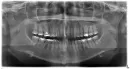

Пошла в стоматологию, где лечила 5-ый зуб, не могли определить, что болит, 5-ый зуб или 6-ой соседний. Стучали по зубу, не реагирует. Только реакция на воздух. Отправили на панорамный снимок зубов, после этого врач сказала скорее проблема в 6-ом зубе. Отправили на ЭОД, сделали 3-и зуба, врач написала: 2.5 - 15 мкА, 2.6 - 190 мкА, 2.7 - 5 мкА. Написала так: обострен. хрон. фиброз периодонт.

Пошла в клинику, где делали 5-ый зуб, там пришло время пломбировать каналы. Врач не стала мне ничего делать, говорит, у вас болит 6-ой зуб, поэтому трогать 5-ый зуб не будем, пойдет инфекция. Эта врач делала снимок 6-го зуба, сказал, что не допломбированы 2 канала, каналы запломбированы рыхло, так не должно быть, говорит будто не пломбировали. Еще сказала, что у меня, возможно, киста, темное место на снимке между корней. Врач пощупала мне десну, она воспалена и есть какой-то выступ. Я сама потом пальцем трогала, да, на десне что-то выпирает. Говорит нужно идти к хирургу.

Я опять пошла в клинику, где делали 6-ой зуб. Говорю, что боль не проходит, есть не могу и ночью просыпаюсь, видимо надавлю во сне и боль дикая. Врач распломбировала каналы, поставила лекарство (вроде щелочь, калий). Это было вчера. Говорит, каналы она хорошо пломбировала, но 2 сказала не допломбированы, так как сложно пройти, узкие, говорит, так делают. Не обязательно до конца пломбировать. Говорит никакой кисты нет, не переживайте.

Я не знаю, кому верить, одна врач говорит идти к хирургу, другая говорит все хорошо. Видно ли на снимке кисту? Правда, что можно не до конца запломбировали каналы? Правда ли, что канал был запломбирован рыхло, некачественно?

К сожалению, по фотографии судить сложно, прицельный рентгеновский снимок не достаточно хорошего качества, границы кисты не определяются.